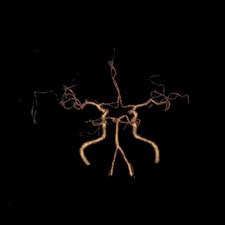

脑动脉开窗畸形通常在尸检或者影像学检查时被发现。CTA和MRA不仅能够无创地显示开窗畸形的位置、形态和毗邻结构,还能显示伴发的其它病变,是脑动脉开窗畸形2种最佳的诊断方法。当脑动脉开窗畸形难以跟动脉夹层进行鉴别时,可以考虑行脑血管造影检查,进行三维重建便可进一步帮助鉴别。